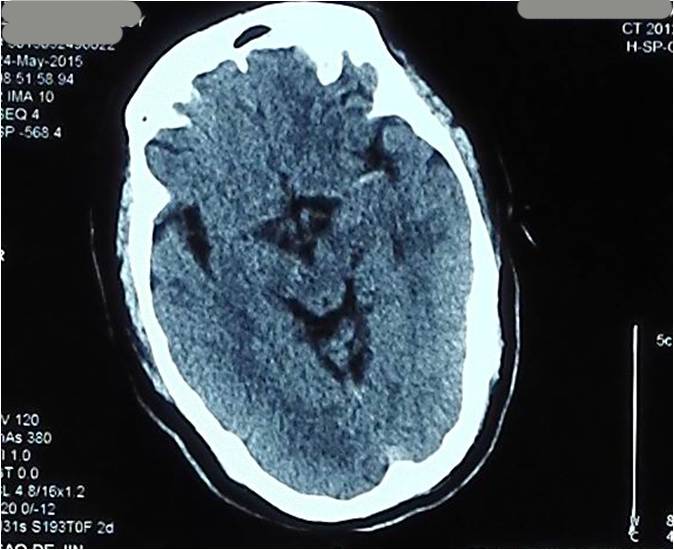

Case5 术后过度灌注、出血转化

》47岁,男,既往吸烟史20年

》12:00末次正常,15:00被发现言语不清、右侧肢体无力

》18:30到达急诊科,NIHSS 14分

》18:39完成头CT检查,19:28头MRA检查

》19:50行股动脉穿刺

》21:48结束手术

》术后24h NIHSS 8分

▼术前CT

▼术前MRA

▼术中给予替罗非班

▼术后24h头CT

▼术后72h 病情恶化,脑疝形成

▼去骨瓣减压,死亡